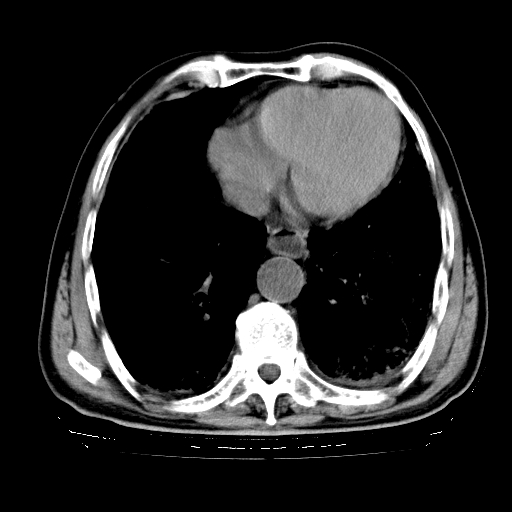

标题: CT25149:男,69岁,反复咳嗽、咳痰五年余,呼吸困难三天。 [打印本页]

男,69岁,反复咳嗽、咳痰五年余,呼吸困难三天。

慢支伴感染、肺气肿、肺心病

慢支伴感染、肺气肿、肺心病!支持!另:间质纤维化!

慢支伴感染、肺气肿、肺心病。双肺间质性改变(间质纤维化)。